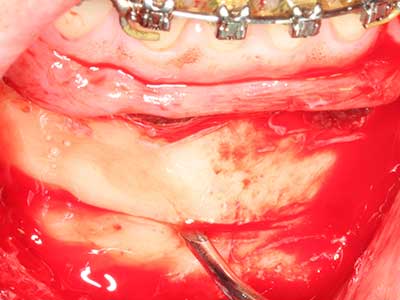

When surgical procedures are performed on bone in the immediate vicinity of sensitive structures such as blood vessels or nerves, rotary instruments pose a significant risk of iatrogenic injury. Piezoelectric devices can be helpful for preparation of bone covers and removal of hard tissue close to nerves, particularly for exposure of nerves after iatrogenic injury but also during nerve lateralization for resective and reconstructive procedures or implant placement (Fig. 17-20). Light contact between the piezotip and the nerve does not generally result in damage but proceeding incautiously with saw-like motions or attachments where a residual bone substrate remains may cause temporary or even permanent nerve damage. However, the risk of damage is considered to be substantially lower than when using saws or milling instruments (Pereira, Gealh et al. 2014).

As shown in the past, basically any bone surgery procedure represents a possible indication for piezo surgery. Thus preparation of the mobile segment in distraction osteogenesis (Fig. 23-25) and sandwich osteotomy uses special attachments without endangering the blood supply to the crestal section, which is essential for the success of both techniques (Gonzalez-Garcia, Diniz-Freitas et al. 2008).